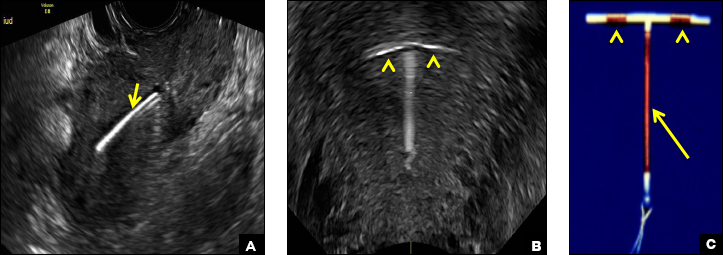

Skyla (Bayer) and Kyleena (Bayer) are small-framed LNG-IUDs. The ultrasound appearance of Skyla (LNG 13.5 mg) is similar to that of Mirena but has a markedly echogenic silver ring superiorly just below the crossbar, best seen with 2D (sagittal) views but also imaged with 3D ultrasound.1,2,5

The Kyleena device (LNG 19.5 mg) uses the same smaller T-shaped frame and metal ring, but the plastic sleeve is longer to accommodate the greater quantity of progestin.6